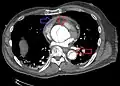

Computed tomography

Computed tomography angiography is a fast, non-invasive test that gives an accurate three-dimensional view of the aorta. These images are produced by taking rapid, thin-cut slices of the chest and abdomen, and combining them in the computer to create cross-sectional slices. To delineate the aorta to the accuracy necessary to make the proper diagnosis, an iodinated contrast material is injected into a peripheral vein. Contrast is injected and the scan performed using a bolus tracking method. This type of scan is timed to injection to capture the contrast as it enters the aorta. The scan then follows the contrast as it flows through the vessel. It has a sensitivity of 96 to 100% and a specificity of 96 to 100%. Disadvantages include the need for iodinated contrast material and the inability to diagnose the site of the intimal tear.

-

CT with contrast demonstrating aneurysmal dilation and a dissection of the ascending aorta (type A Stanford) -

Chest CT with descending (type B Stanford) aortic dissection (red circle)

Type A dissection with pericardial effusion as a result.